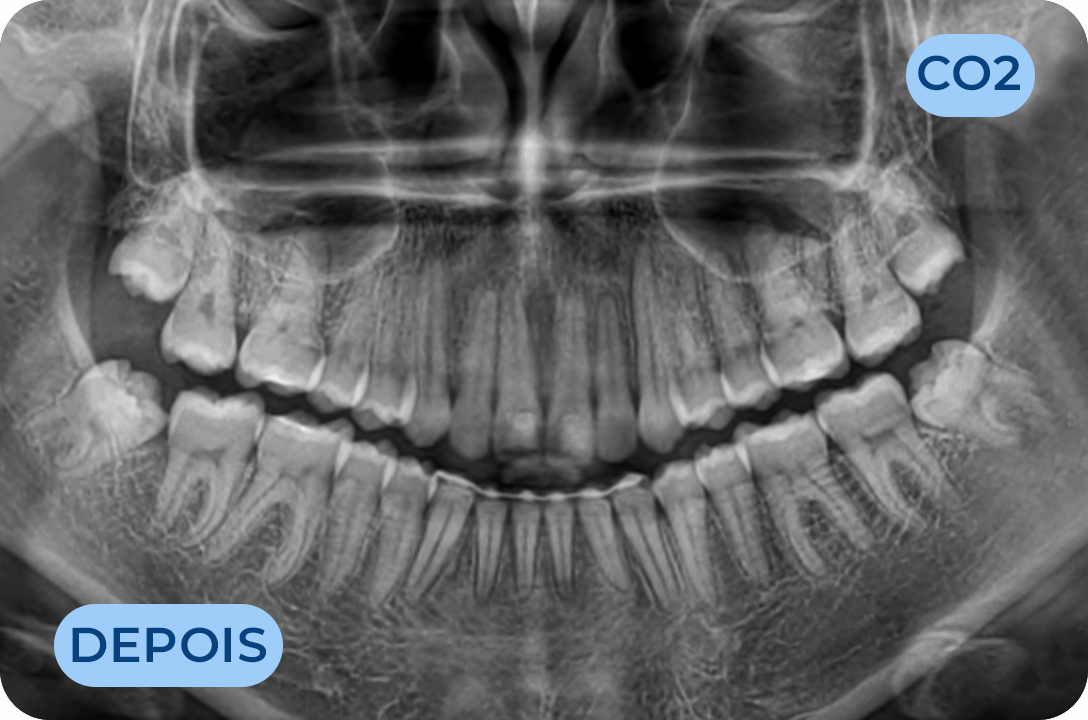

Prostodontia

É a área da Medicina Dentária que atua na substituição de dentes perdidos ou comprometidos esteticamente. Os dentes são substituídos através de dentes fixos (coroas em cerâmica suportadas por implantes ou suportadas por raízes de dentes naturais) bem como próteses removíveis. Mais recentemente surgiram as facetas (lentes de contacto) com a vantagem de conservar mais os tecidos dentários e com ótimos resultados estéticos. É uma área muito importante na reabilitação da função mastigatória assim como da auto estima, recuperando a vontade de sorrir.